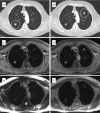

Chest wall invasion by a tumour and mediastinal masses are known to benefit from the superior soft tissue contrast of magnetic resonance imaging (MRI). However, helical computed tomography (CT) (i.e. with multiple row detector systems) remains the modality of choice to detect and follow lesions of the lung parenchyma. Since minimizing radiation exposure plays a minor role in oncologic patients, there are only few routine indications for which MRI of lung parenchyma is preferred to CT. This includes whole body MR imaging for staging or scientific studies with frequent follow-up examinations. MR-based lung imaging in this context was always considered as a weak point. Depending on the sequence technique and imaging conditions (i.e. ability to hold breath) the threshold for lung nodule detection with MRI using 1.5 T systems was estimated to be above 3-4 mm. The feasibility of lung MRI at 0.3-0.5 T and 3.0 T systems has been demonstrated. The clinical value of time-resolved lung nodule perfusion analysis cannot yet be determined, although the combination of perfusion characteristics with morphologic criteria contributes to estimate the integrity of a solitary lesion.